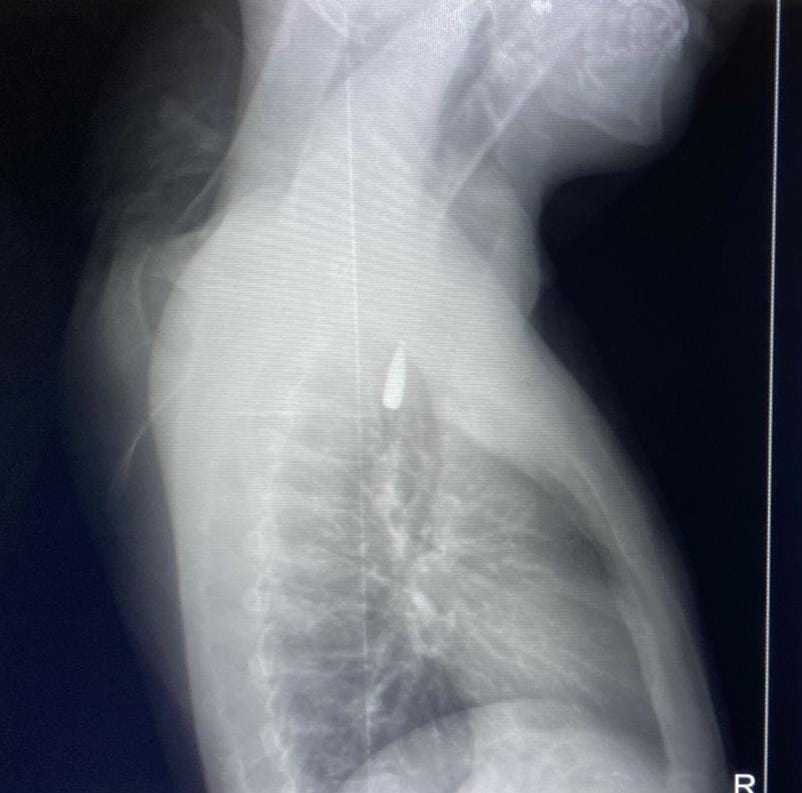

في إنجاز طبي جديد يعكس كفاءة الفرق الطبية المصرية ودورها الإنساني، نجح فريق من أطباء جامعة الإسكندرية في إجراء عملية جراحية دقيقة ونادرة لإنقاذ مريض فلسطيني مصاب بطلق ناري من قطاع غزة، بعد أن استقر المقذوف داخل تجويف القفص الصدري بالقرب من الشريان الأورطي، أحد أخطر وأدق مناطق الجسم.

ومن جانبه، أوضح الدكتور تامر عبد الله، عميد كلية الطب ورئيس مجلس إدارة المستشفيات الجامعية، أن العملية أُجريت يوم 21 أكتوبر الجاري داخل المستشفى الجامعي الجديد، بمشاركة فريق من جراحي القلب والصدر وأطباء التخدير، واستمرت عدة ساعات وسط ظروف دقيقة ومعقدة، قبل أن ينجح الفريق في استخراج المقذوف بأمان تام. وأشار إلى أن المريض يتلقى حاليًا الرعاية الطبية الكاملة، وحالته مستقرة وتحت الملاحظة الدقيقة.